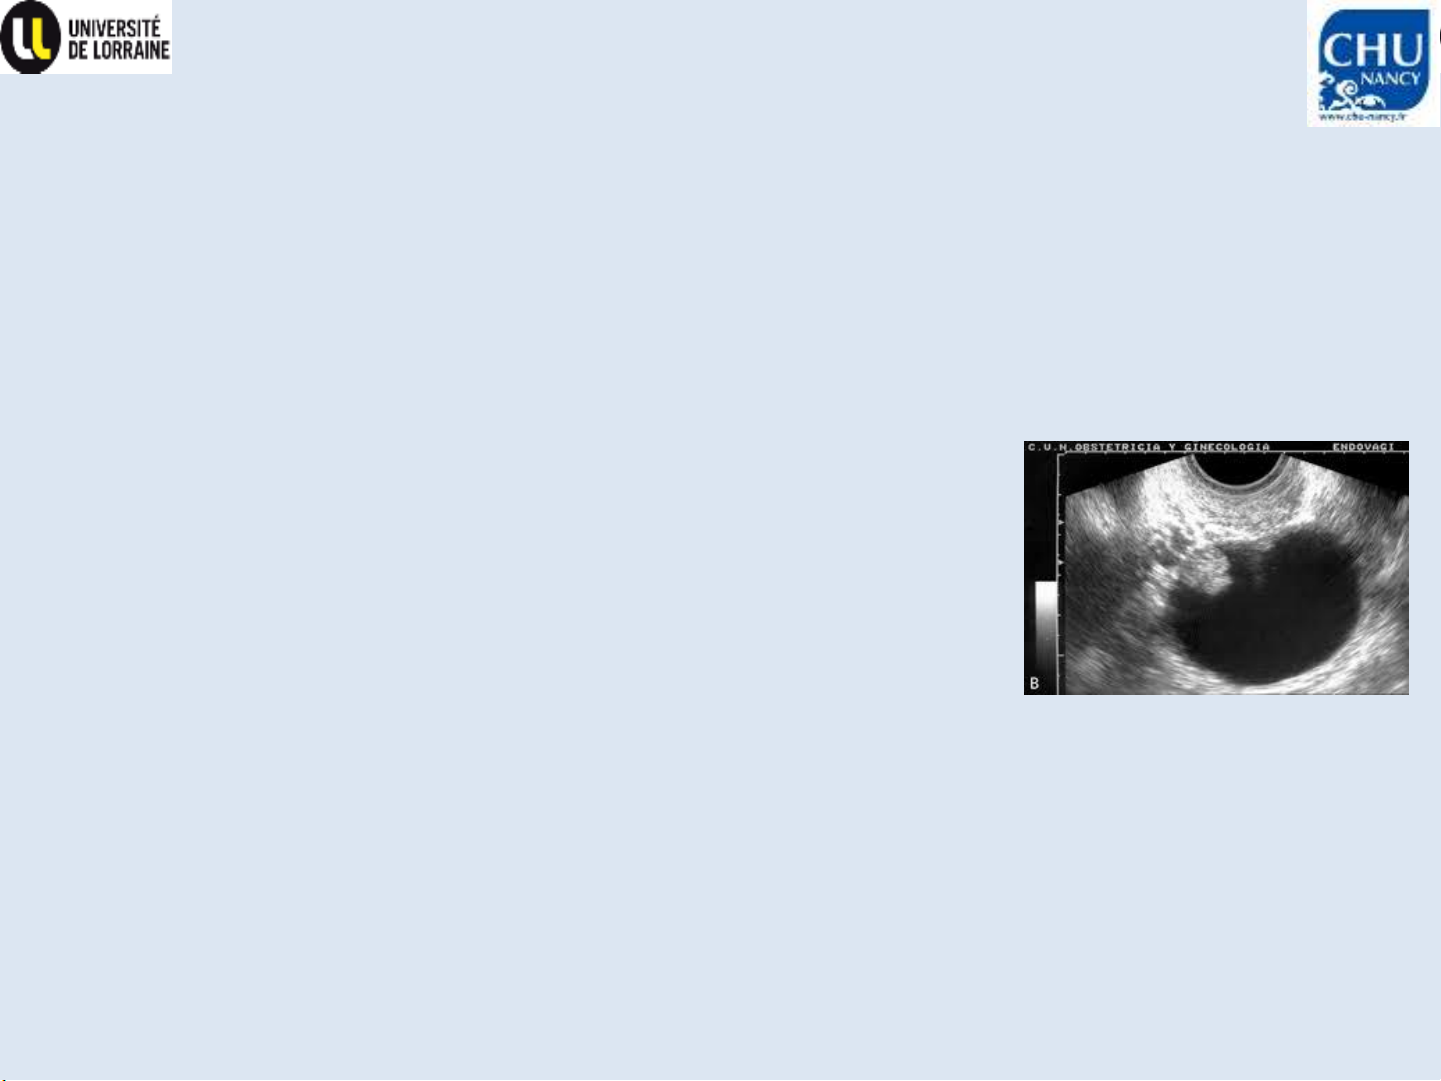

Nghi ngờ ung thu buồng trứng

•Hình ảnh

–Chụp CLVT ngực-bụng-tiểu khung

–±CHT tiểu khung (bổ sung cho siêu âm)